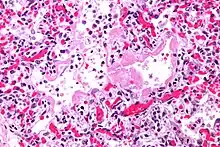

| Micrograph of diffuse alveolar damage, the histologic correlate of TRALI; H&E stain | |